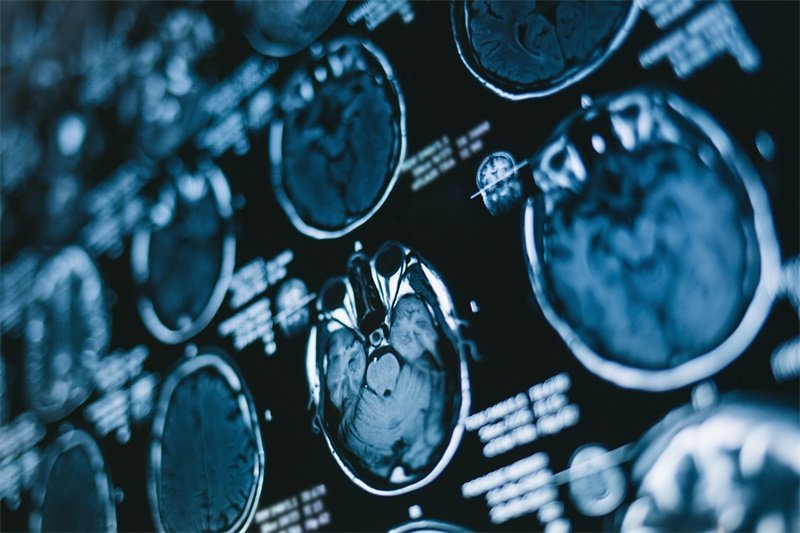

1.磁共振成像(MRI):是诊断的金标准,可清晰显示占位病变的位置、大小、形态、与周围神经血管的关系及病变性质。不同病变在MRI上表现各异,如听神经瘤在T1加权像上多为低信号,T2加权像上呈高信号;脑膜瘤增强扫描后明显强化。

2.计算机断层扫描(CT):可快速发现病变,对判断是否有骨质破坏、钙化及出血等情况有优势,常作为初步筛查手段。